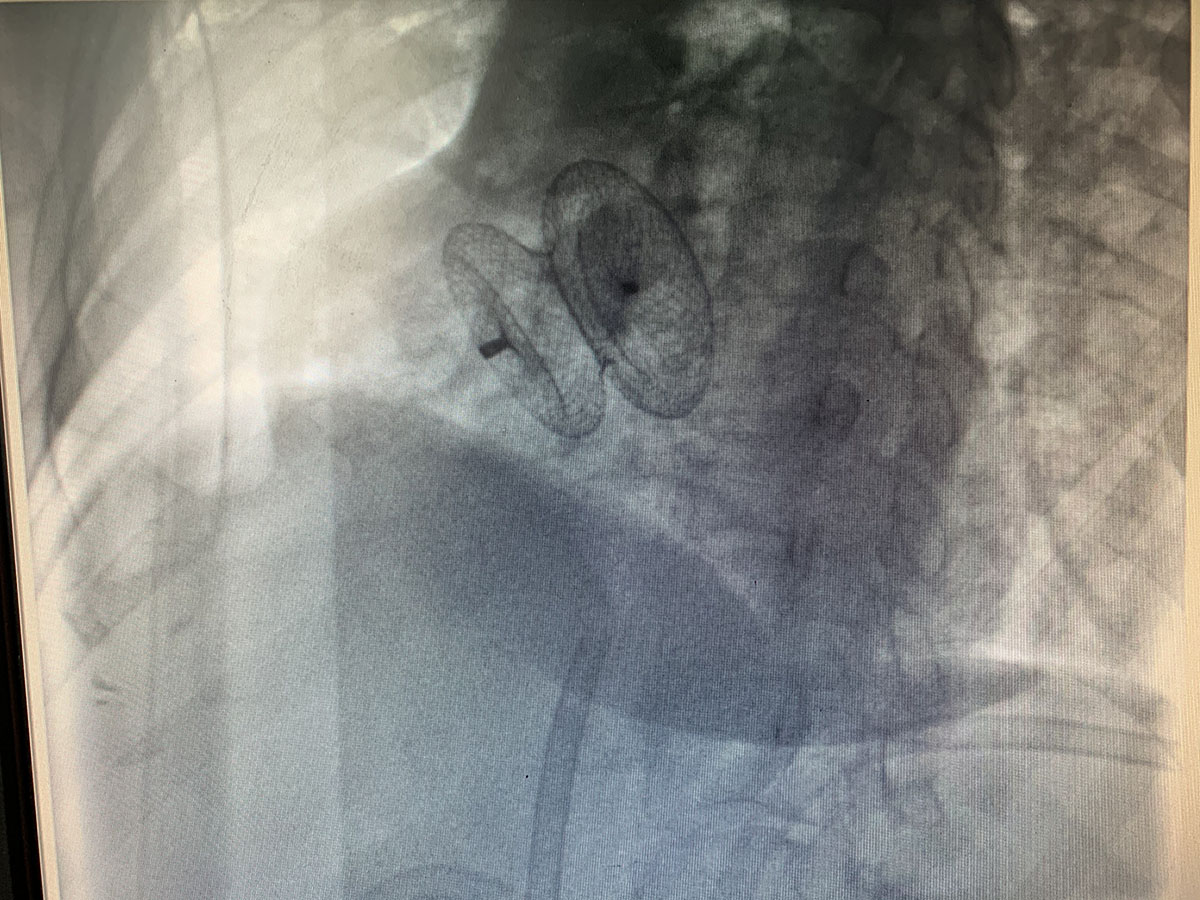

據(jù)了解,王女士,45歲,以發(fā)作性喘息伴胸悶氣短10天,加重1天入住周口市中醫(yī)院心內(nèi)科。患者既往發(fā)現(xiàn)先天性心臟病房間隔缺損10余年,未予重視。入院后經(jīng)行相關生化檢查,心臟彩超,胸片,確診為:房間隔缺損 心力衰竭 心功能III級。于2019年12月14日于我科行房間隔缺損封堵術,手術順利。現(xiàn)已康復出院。